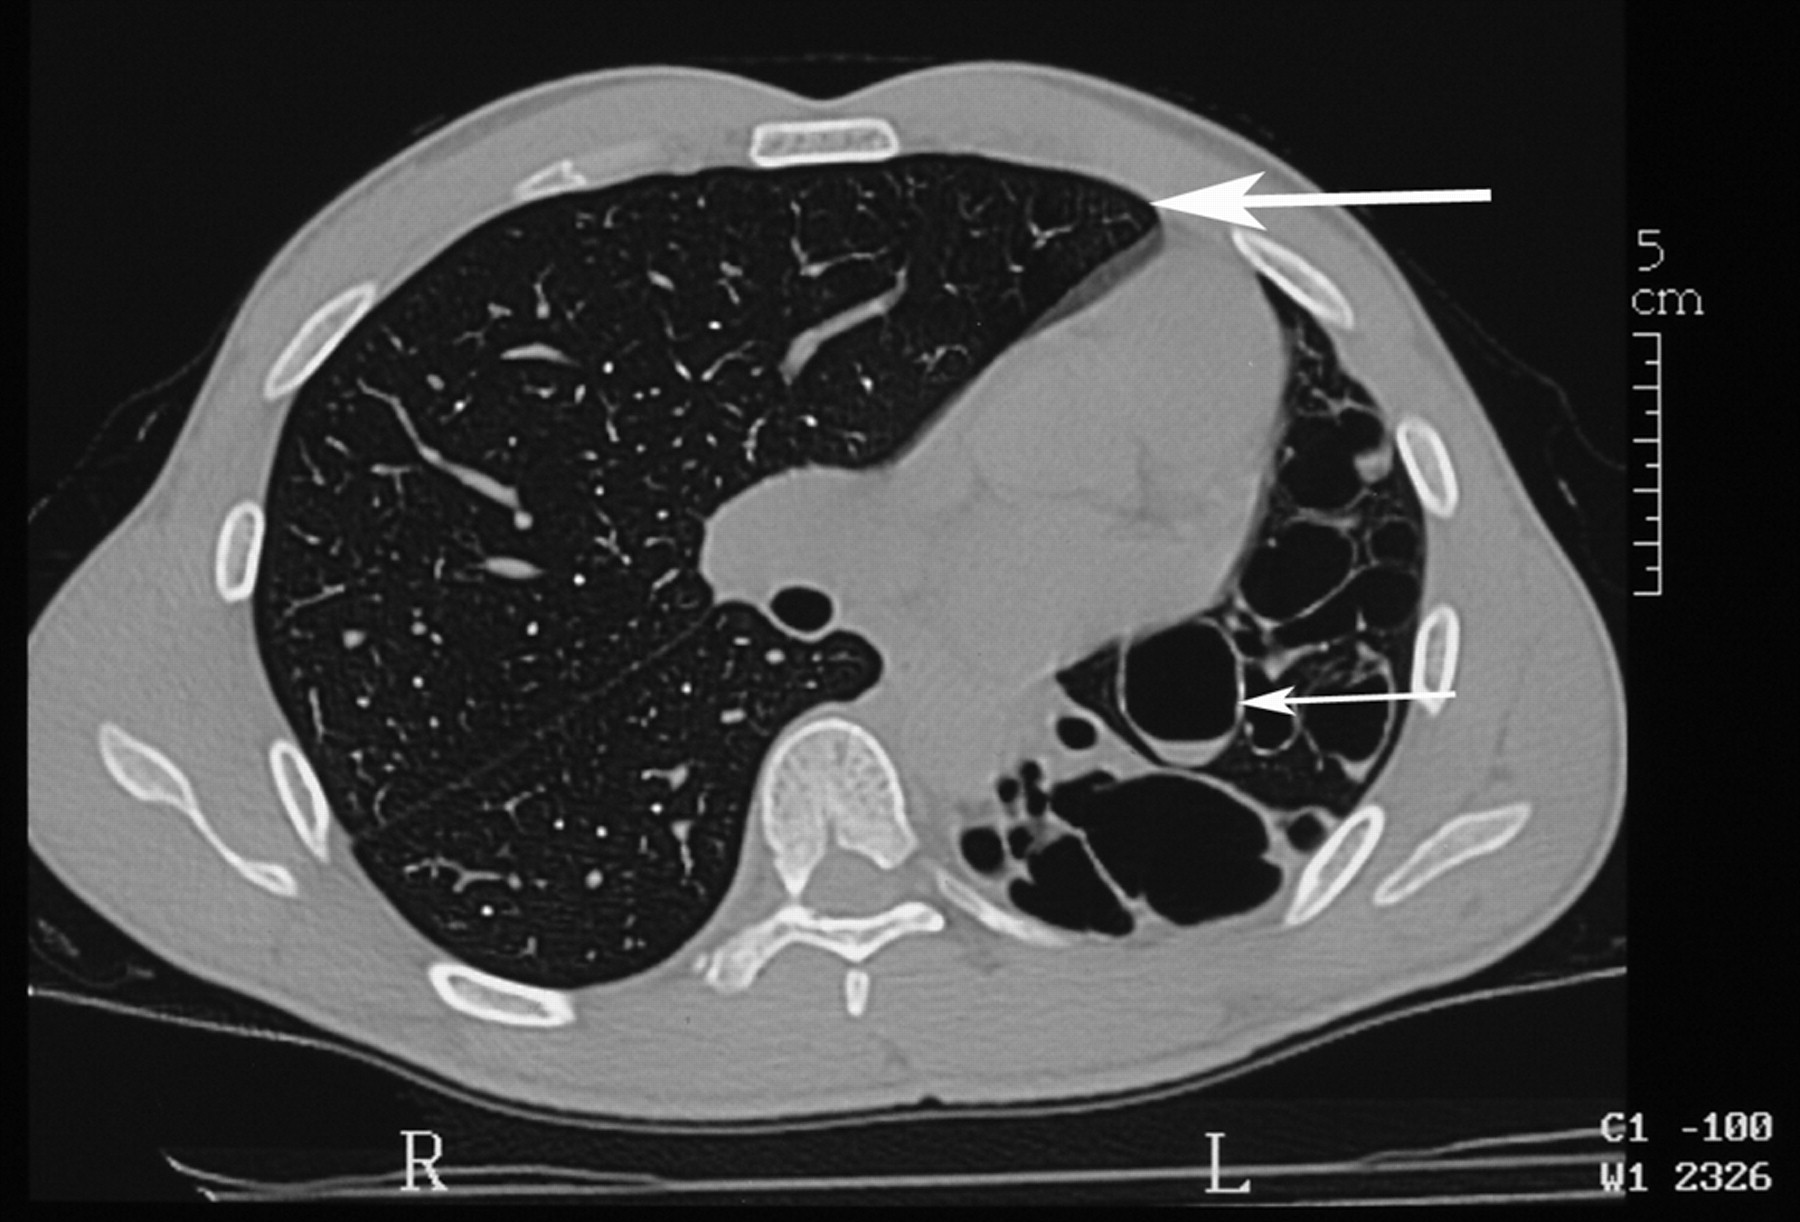

Секвестрация легкого

На компьютерных томограммах в заднемедиальном отделе нижней доли левого легкого виден участок повышенной воздушности, легочный рисунок в нем деформирован, не прослеживаются просветы сегментарных бронхов, нет дренирующего бронха.

"Секвестрированный" участок в заднемедиальном отделе нижней доли левого легкого кровоснабжается аномальной артерией, отходящей от аорты.